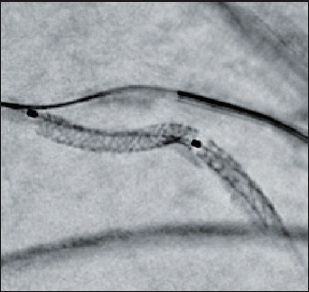

Stent Enhancer* забезпечує візуалізацію стента за рахунок придушення анатомічних структур та фонового шуму.

Stent Mode забезпечує покращену візуалізацію стента в реальному часі без необхідності додаткової окремої обробки або післяобробки.